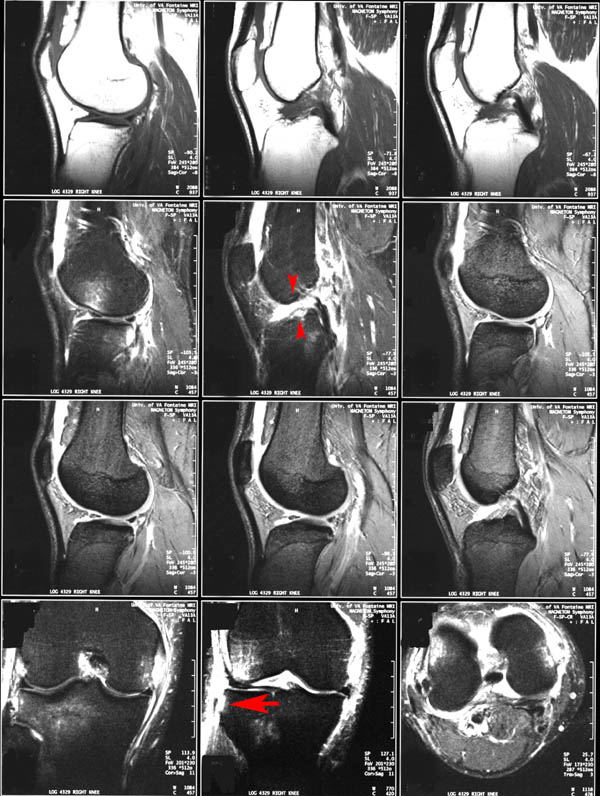

• Due to the mechanism of injury, anterior cruciate ligament tears are commonly associated with this type of fracture.

MRI of a segond fracture (arrow) and ACL tear (arrowheads)